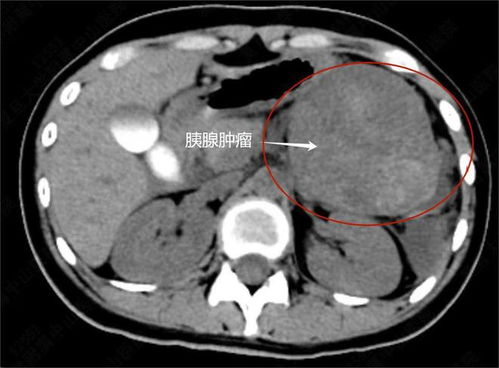

胃癌悲剧:孩子无辜受害,二手烟的隐形杀手 明知道吸烟有害健康,但是很多烟民就是不想戒烟,甚至还在家里肆无忌惮的吸烟,根本不考虑二手烟会不会危害孩子的健康。 悲剧案例:13岁女孩胃癌晚期,罪魁祸首竟是二手烟 最近,河南省肿瘤医院消化科就接诊了一名年仅13岁的胃癌晚期女孩。医生向记者介绍,女孩之所以患上胃癌,是因为她爸爸常年吸烟,在家也从来没有避开过孩子,使得孩子从小生活在充满二手烟的环境里。 医生痛心疾首:孩子腹腔布满肿瘤,无治愈机会 让医生都心痛到愤怒:“给孩子做手术,腹腔打开又关上了,根本没法手术,全身多发转移,腹腔像撒豆子一样布满了大大小小的肿瘤,这种是没有任何治愈机会的。” 二手烟的危害:被动吸烟者同样受害,尤其对儿童影响严重 二手烟是被动吸烟的俗称,不吸烟者每日被动吸烟15分钟以上,就被认定为被动吸烟。吸烟的危害甚重,而二手烟对被动吸烟者的危害不比主动吸烟者轻,特别是对少年儿童的危害尤其严重。 谣言粉碎:胃癌与二手烟的关系不容忽视 很多人第一反应是不信,觉得胃癌要么是遗传,要么是吃出来的,跟二手烟能有多大关系。其实世界范围内的多项研究已经证明,吸烟是癌症、心脑血管疾病、中风、高血压等多种疾病的致病因子,除了密切相关的肺癌,还可能与宫颈癌、结直肠癌、膀胱癌、食道癌、胃癌等等相关。